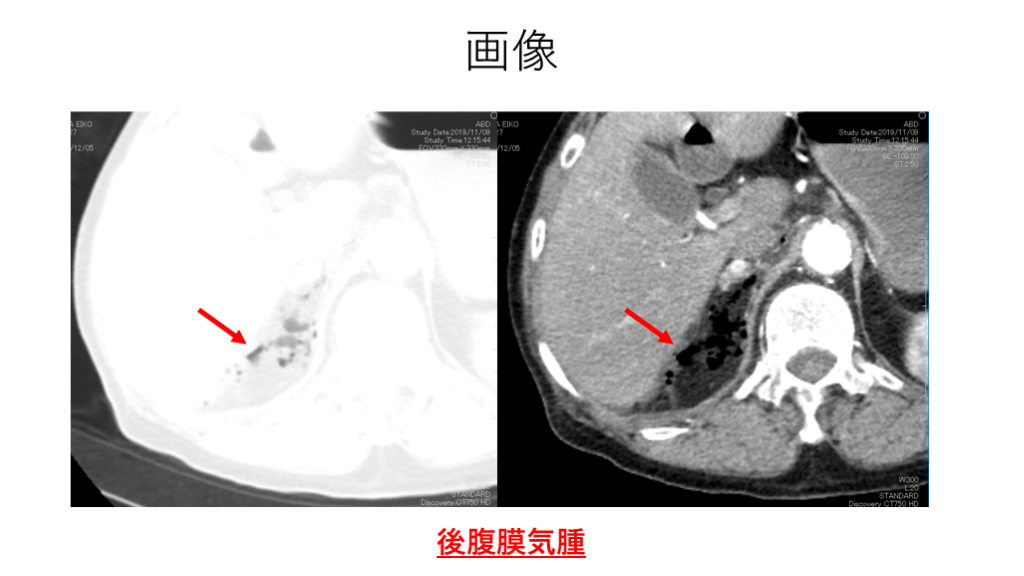

画像 後腹膜気腫

画像 肺野条件(F5)で確認すれば後腹膜気腫を同定できた可能性がある。

画像 右後腎傍腔の液体貯留・少量気腫を認めている。

考察 ・腸閉塞の疑いでコンサルテーションされ、臨床症状と  画像所見で麻痺性イレウスと診断した。 ・麻痺性イレウスの原因を透析患者に度々生じる腸管麻痺  と判断し、画像中に原因がないか検索する必要があった。 ・肺野条件でairを検索していれば後腹膜気腫を特定できた  可能性があった。